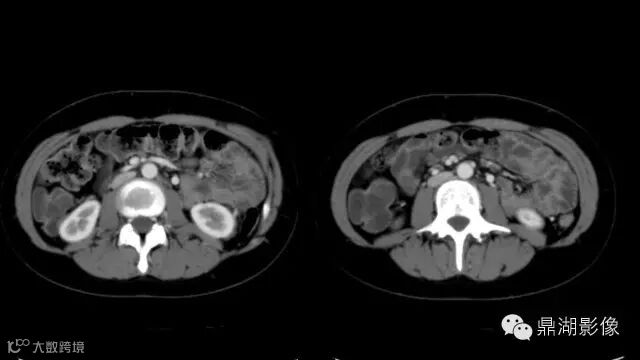

do you know comb sign?

The comb sign refers to the hypervascular appearance of the mesentery in active Crohn disease.

Very impressive image